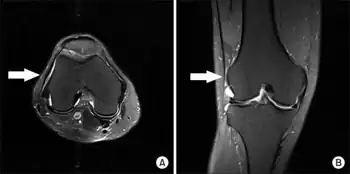

Iliotibial band syndrome (ITBS) is the second most common knee injury, and is caused by inflammation located on the lateral aspect of the knee due to friction between the iliotibial band and the lateral epicondyle of the femur.[2] Pain is felt most commonly on the lateral aspect of the knee and is most intensive at 30 degrees of knee flexion.[2] Risk factors in women include increased hip adduction and knee internal rotation.[2][3] Risk factors seen in men are increased hip internal rotation and knee adduction.[2] ITB syndrome is most associated with long-distance running, cycling, weight-lifting, and with military training.[4][5]

Anatomical mechanism

Iliotibial band syndrome is one of the leading causes of lateral knee pain in runners. The iliotibial band is a thick band of fascia on the lateral aspect of the knee, extending from the outside of the pelvis, over the hip and knee, and inserting just below the knee. The band is crucial to stabilizing the knee during running, as it moves from behind the femur to the front of the femur during activity. The continual rubbing of the band over the lateral femoral epicondyle, combined with the repeated flexion and extension of the knee during running may cause the area to become inflamed.[9]

Diagnosis of iliotibial band syndrome is based on history and physical exam findings, including tenderness at the lateral femoral epicondyle, where the iliotibial band passes over the bone.[10]